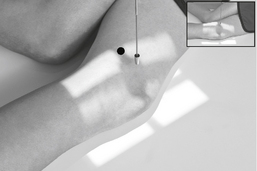

• Supine or seated, dorsiflex foot to as near vertical position as possible. If possible, have patient pull on gauze as shown. (This may be painful for patient to maintain, don’t delay!)